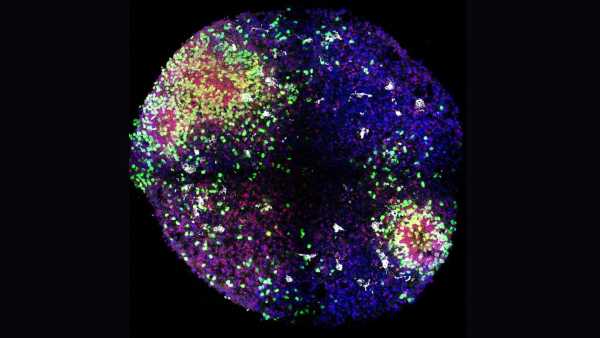

«Мінімозки» розкривають секрети формування ключових клітин мозку в утробі матері

«Мінімозки» розкривають секрети формування ключових клітин мозку в утробі матері

«Мінімозки» розкривають секрети формування ключових клітин мозку в утробі матері